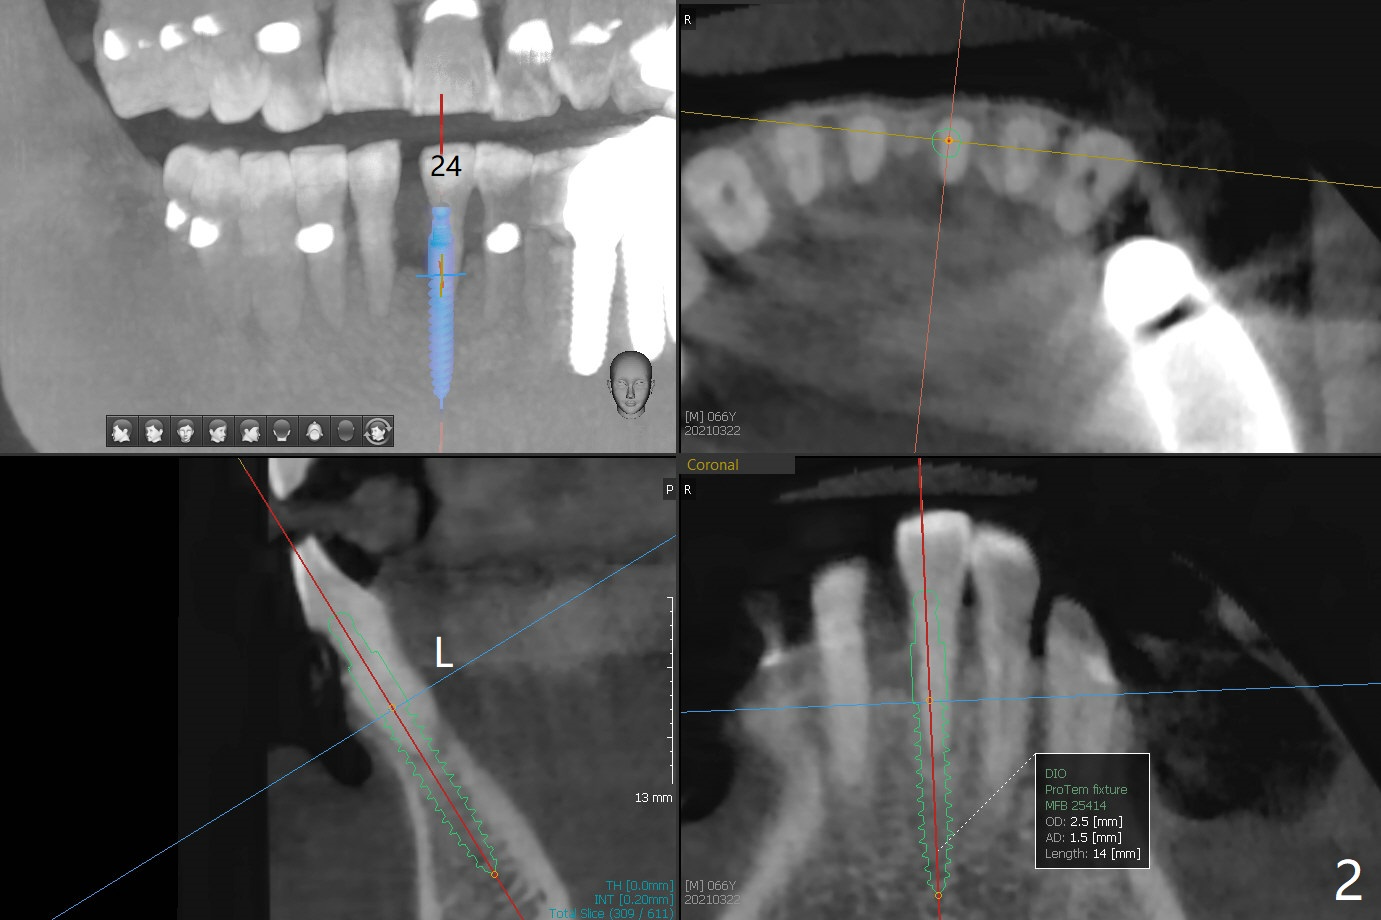

A 66-year-old man requests implant placement at #24, 30 and 31 (Fig.1). Bone loss at #19 and 24 lingual (Fig.2) suggests bruxism. The implant at #24 will be as buccal and mesial (to close the diastema between 24 and 25 (Fig.1 *)) as possible (Fig.2). The vertical space for restoration of 30 and 31 implants (Fig.3,4) is limited; the cusps of the opposing teeth may need to be trimmed.